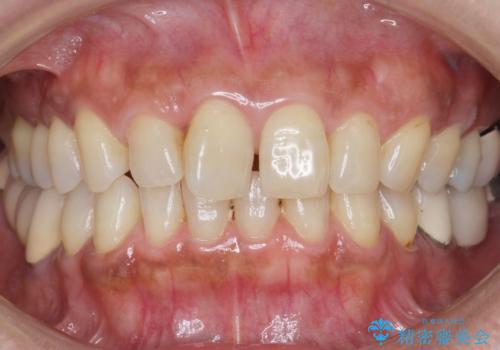

根管治療後、メタルボンドブリッジによる補綴治療を行いました。

自然な仕上がりと咬み心地に喜んで頂けました。

クラウンの種類:メタルボンドクラウン エコノミー